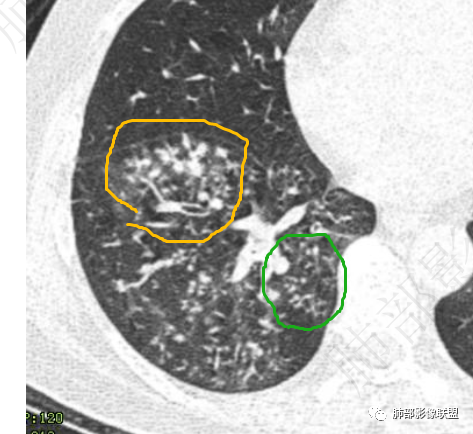

黄色、绿色啥差异?大小?什么意思?

就是病灶因为炎性反应,渗出、增生,会融合。

小树芽——增大,与旁边的病灶融合,形成大病灶。再融合——再增大。金葡菌发展速度快,很快就是一个大病灶,呈叶段性改变。

57岁男性,糖尿病、肾病基础。白细胞升高、以中性升高为主,黄浓痰提示细菌感染、球菌可能大。结核几次相关检查都阴性,可能性不大。几次血培养无细菌生长,结合影像,病灶不是血播而是气道播散。影像:沿气道播散,树芽明显,(树芽有没有特征?部分枝细芽大?),部分支气管弥漫增厚,治疗10后复查,临床没有怀疑真菌类,结核阴性,所以抗结核抗真菌的可能小,只能是抗炎治疗10天后复查,树芽缩小、部分消散,支气管壁变薄,提示抗菌有效,但部分出现了气囊空洞。细菌、空洞、黄浓痰,加起来,首先考虑金葡菌支气管播撒应该顺理成章。